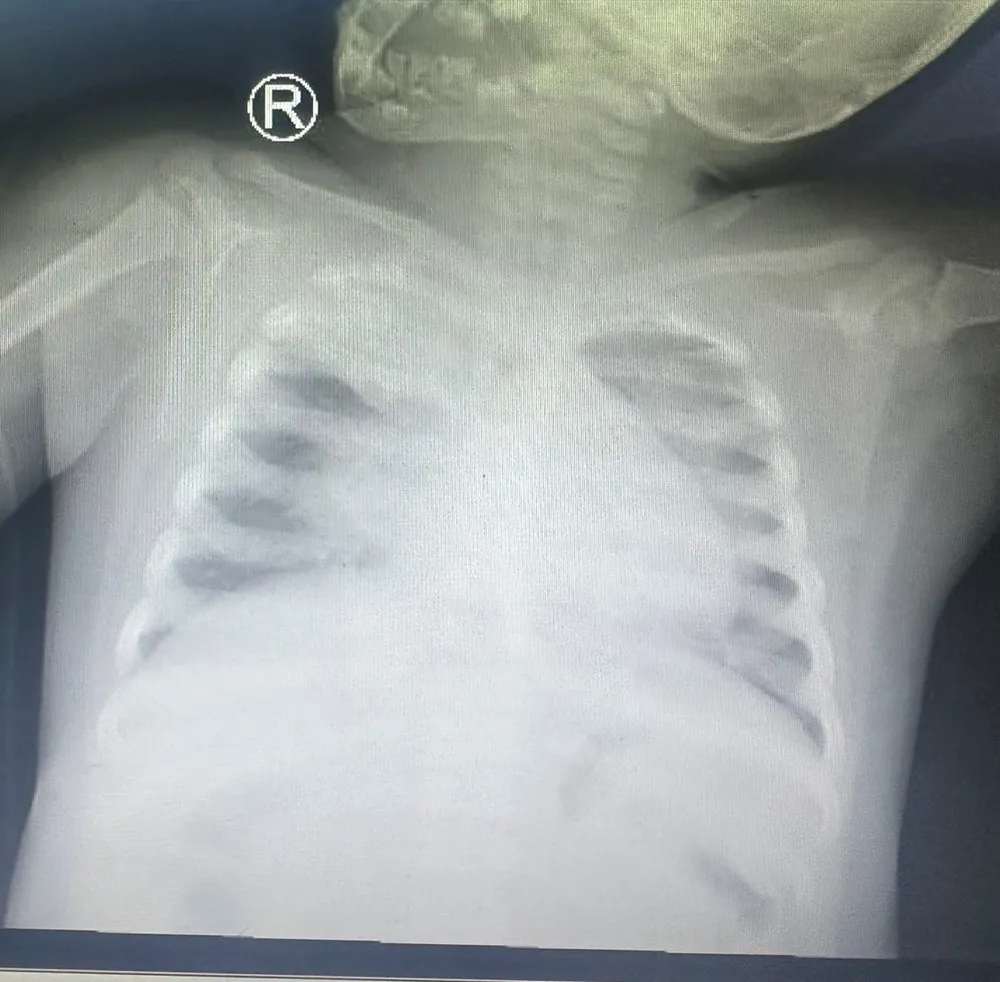

Theo BSCK2 Nguyễn Minh Tiến, Phó Giám đốc Bệnh viện Nhi đồng TP, bệnh nhi nhập viện trong tình trạng li bì tím tái, SpO2 khoảng 80-82%. Kết quả Xquang phổi ghi nhận tình trạng tổn thương lan tỏa 2 bên phổi, xẹp đỉnh phổi. Bệnh nhi được chẩn đoán viêm phổi và suy hô hấp cấp tiến triển nặng do cúm A/H1.

Kết quả Xquang phổi ghi nhận tổn thương lan tỏa 2 bên phổi